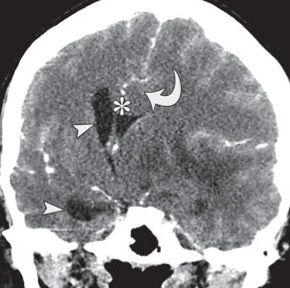

蛛网膜下腔出血影像表现

*仅供医学专业人士阅读参考蛛网膜下腔出血影像表现 医学界医生站APP「疫情动态」,带你第一时间了解新冠疫情最新学术进展,长按下方图片二维码即可查看。本文首发:粤C影像科责任编辑:孙颖版权申明 本文转载 欢迎转发朋友圈- End -*医学界力求其发表内容在审核通过时的准确可靠,但并不对已发表内容的适时性,以及所引用资料(如有)的准确性和完整性等作出任何承诺和保证,亦不承担因该些内容已过时、所引用资料可能的不准确或不完整等情况引起的任何责任。请相关各方在采用或者以此作为决策依据时另行核查。...